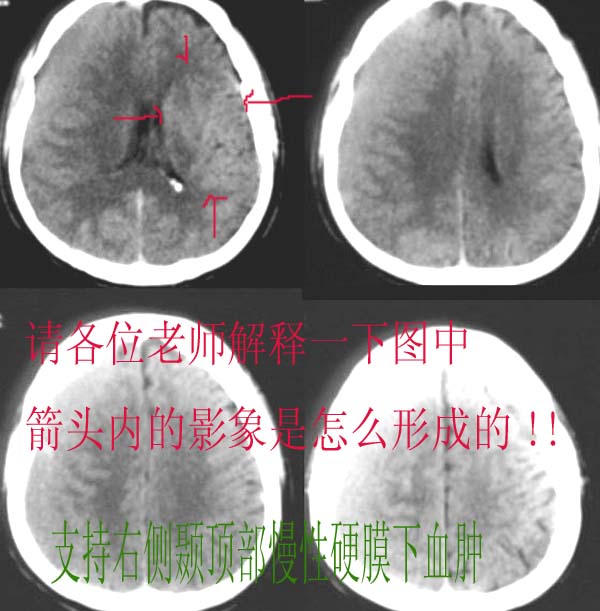

以下是引用dyqct在2006-11-13 14:57:00的发言:[br]我考虑为该病人位置不标准所形成,不知下面图示是否解释清楚。[br][br][br][br]